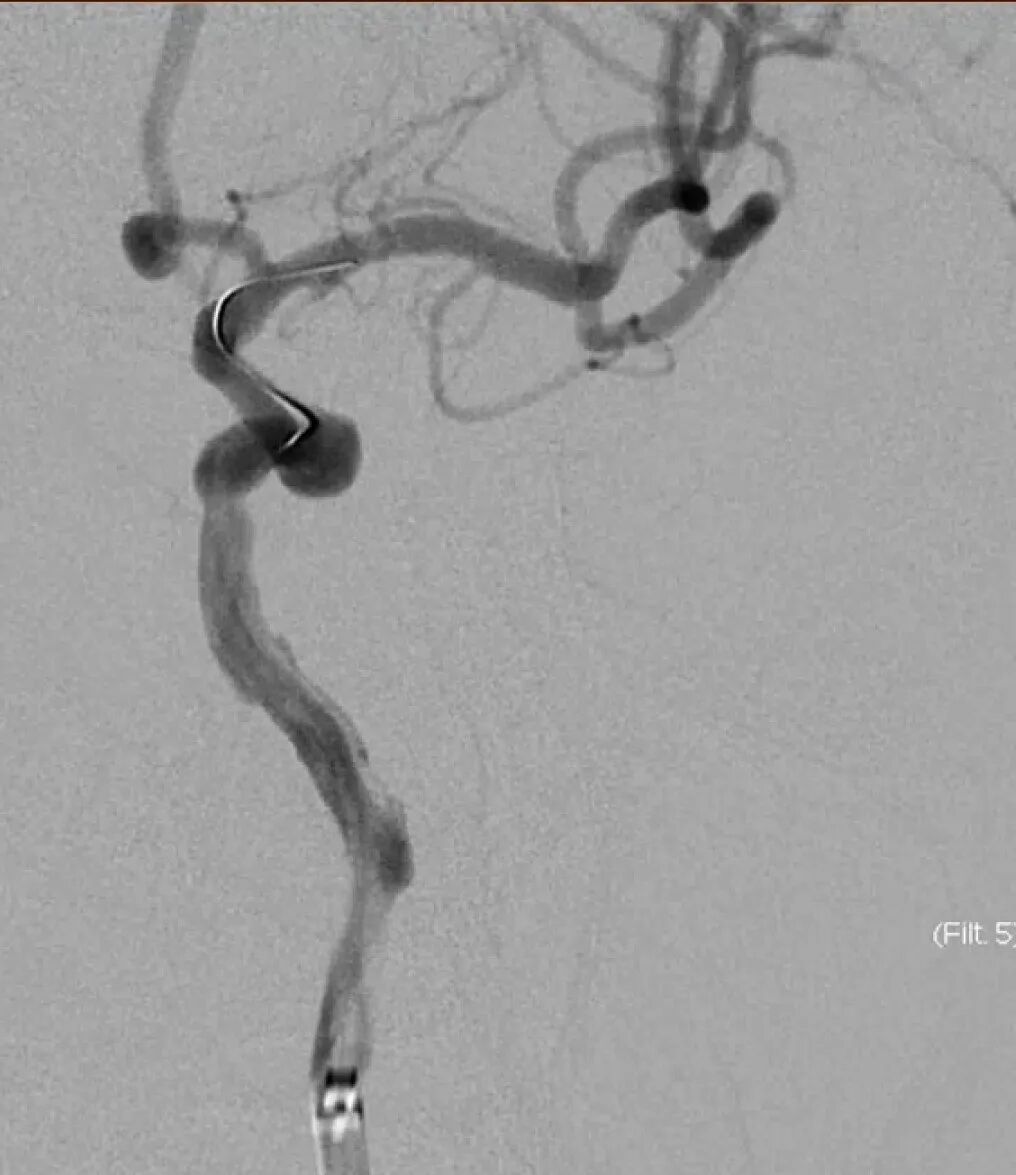

4mm×30mm Streamline

术后4月余随访:多发动脉瘤均未见显影,远端残余轻度狭窄

术前术后对比